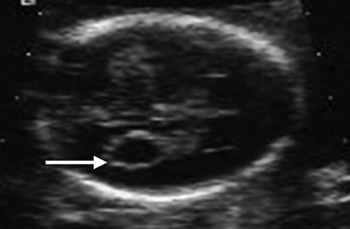

Σύνδρομo Dandy-Walker

Συχνότητα: 1/30.000 γεννήσεις.(6)

ECHO - ευρήματα στο 2ο τρίμηνο:(17,34,40)

- Έλλειψη ή υποπλασία του μίσχου της παρεγκεφαλίδας, με ταυτόχρονη απομάκρυνση των ημισφαιρίων της.

- Κύστη οπισθίου βόθρου.

- Διάταση 4ης κοιλίας που καταλαμβάνει και διατείνει τον οπίσθιο βόθρο.

- Διεύρυνση μεγάλης δεξαμενής εγκεφάλου.

Συνυπάρχουν συχνά (50-70%):(6,23)

- Πολυδακτυλία.

- Ανωμαλίες προσώπου.

- Ανωμαλίες καρδιαγγειακού.

- Ανωμαλίες ουροποιητικού.

- Υδροκεφαλία (50%).

- Ατρησία τρήματος Magendie, Luschka.

Πρόγνωση: Πτωχή, με αυξημένη θνησιμότητα τους πρώτους μήνες της ζωής. Πνευματική υστέρηση στην πλειοψηφία των επιζώντων.